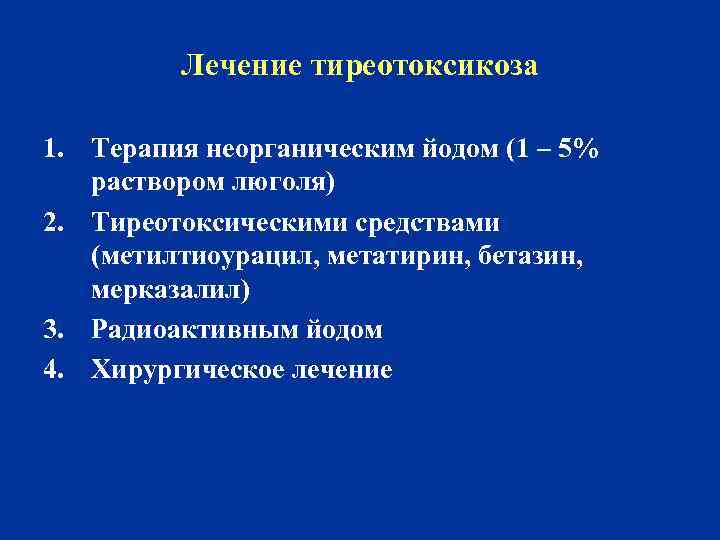

Лечение тиреотоксикоза 1. Терапия неорганическим йодом (1 – 5% раствором люголя) 2. Тиреотоксическими средствами (метилтиоурацил, метатирин, бетазин, мерказалил) 3. Радиоактивным йодом 4. Хирургическое лечение

Лечение тиреотоксикоза 1. Терапия неорганическим йодом (1 – 5% раствором люголя) 2. Тиреотоксическими средствами (метилтиоурацил, метатирин, бетазин, мерказалил) 3. Радиоактивным йодом 4. Хирургическое лечение